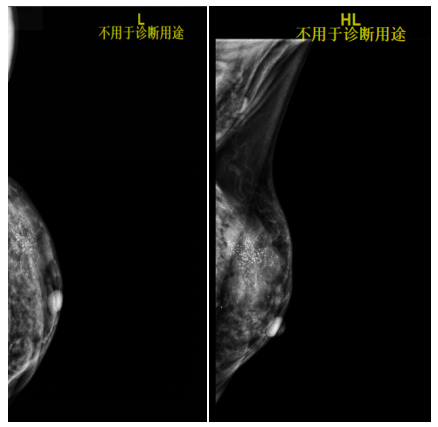

2021.6.9乳腺钼靶片提示:两侧乳腺呈不均匀致密型(ACRc),双乳腺体组织呈弥漫类结节改变。左乳外上象限见一分叶状肿块,边缘少许毛刺,大小约4.5cm×3.5cm,内见成簇细沙样钙化影,邻近皮下脂肪层见条索状密度增高、相应皮肤增厚,相应的乳后间隙部分显示欠清晰。右乳内未见明显异常密度结节或肿块形成,右乳内未见钙化灶。两侧腋下多发淋巴结显示(左腋下较多),双侧胸大肌未见异常,右乳皮肤、皮下、乳头、乳晕未见异常。

影像诊断:左乳外上象限占位(BI-RADS 5类),建议进一步检查;右侧乳腺增生(BI-RADS 1类);左侧腋下多发淋巴结显示。

图2.乳腺钼靶片(2021-6-9)